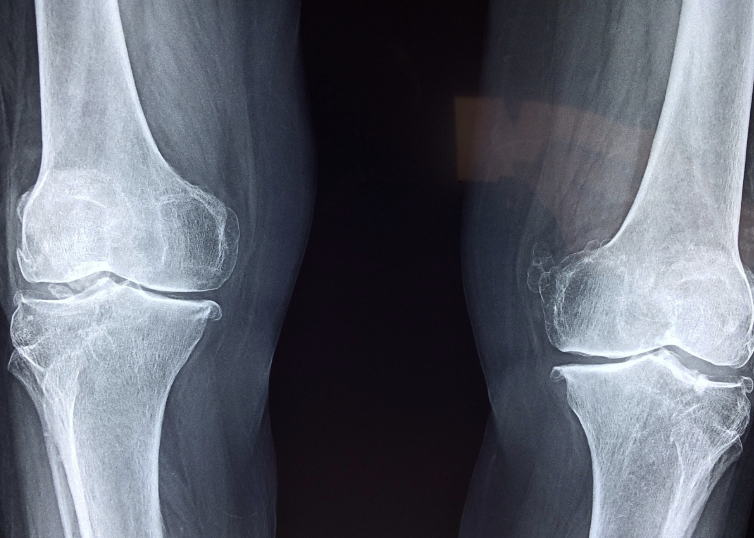

우슬뿌리는 관절 건강을 유지하고 개선하는 데 탁월한 약초로 널리 알려져 있어요. 특히 관절염과 퇴행성 질환으로 인한 통증 완화에 크게 기여하는데, 이는 항염 작용과 혈액 순환 촉진 덕분입니다. 플라보노이드와 사포닌 같은 활성 성분은 관절의 염증을 억제할 뿐만 아니라 연골 건강도 보호해줍니다. 꾸준히 섭취하면 관절 기능이 강화되고 움직임도 유연해질 수 있답니다. 또한, 우슬뿌리 차를 꾸준히 마시는 것이 관절 건강에 특히 좋습니다. (우슬뿌리 먹는법 중 하나인 차는 간단하면서도 효과적이에요.)